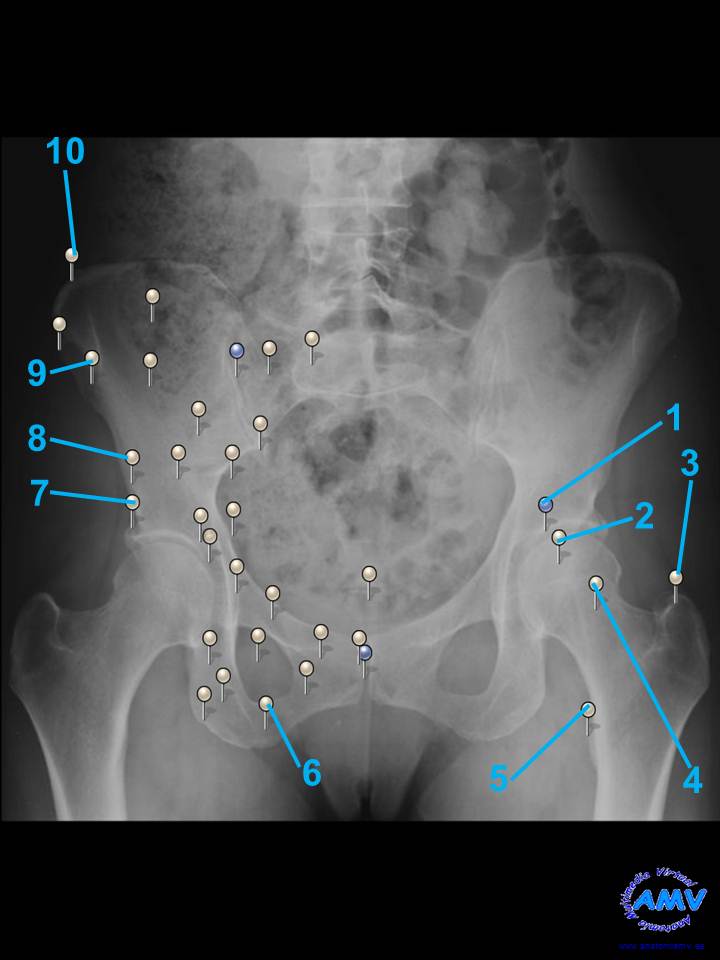

Radiografía Pelvis

rx_mi_02.jpgIndique que estructura se señala con el número correspondiente:

El nº 1 señala .

El nº 2 señala .

El nº 3 señala .

El nº 4 señala .

El nº 5 señala .

El nº 6 señala .

El nº 7 señala .

El nº 8 señala .

El nº 9 señala .

El nº 10 señala .